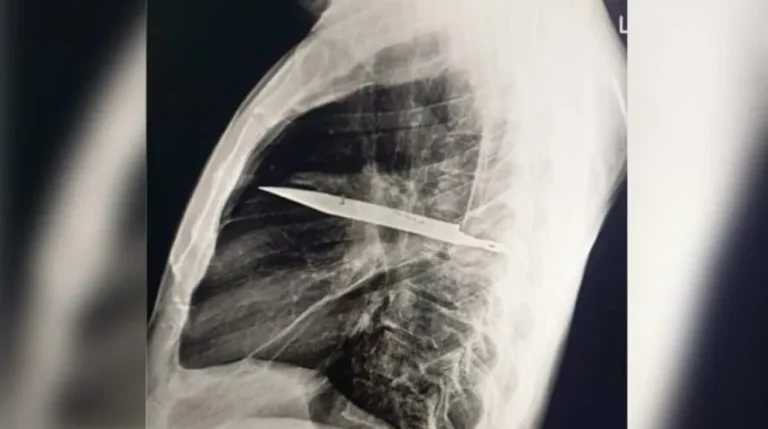

Surpresa no raio-x

O exame atual mostrou que uma lâmina estava presa ao lado direito do tórax, encostada à escápula. Apesar do tamanho, não atingiu órgãos vitais. Segundo os médicos, o acúmulo de pus foi causado pela presença do corpo estranho e por tecido danificado ao redor.